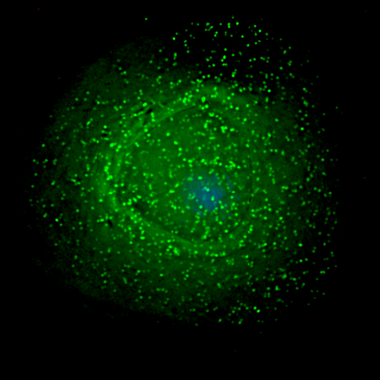

Descubren nuevas dianas terapéuticas y marcadores para el diagnóstico del cáncer de próstata